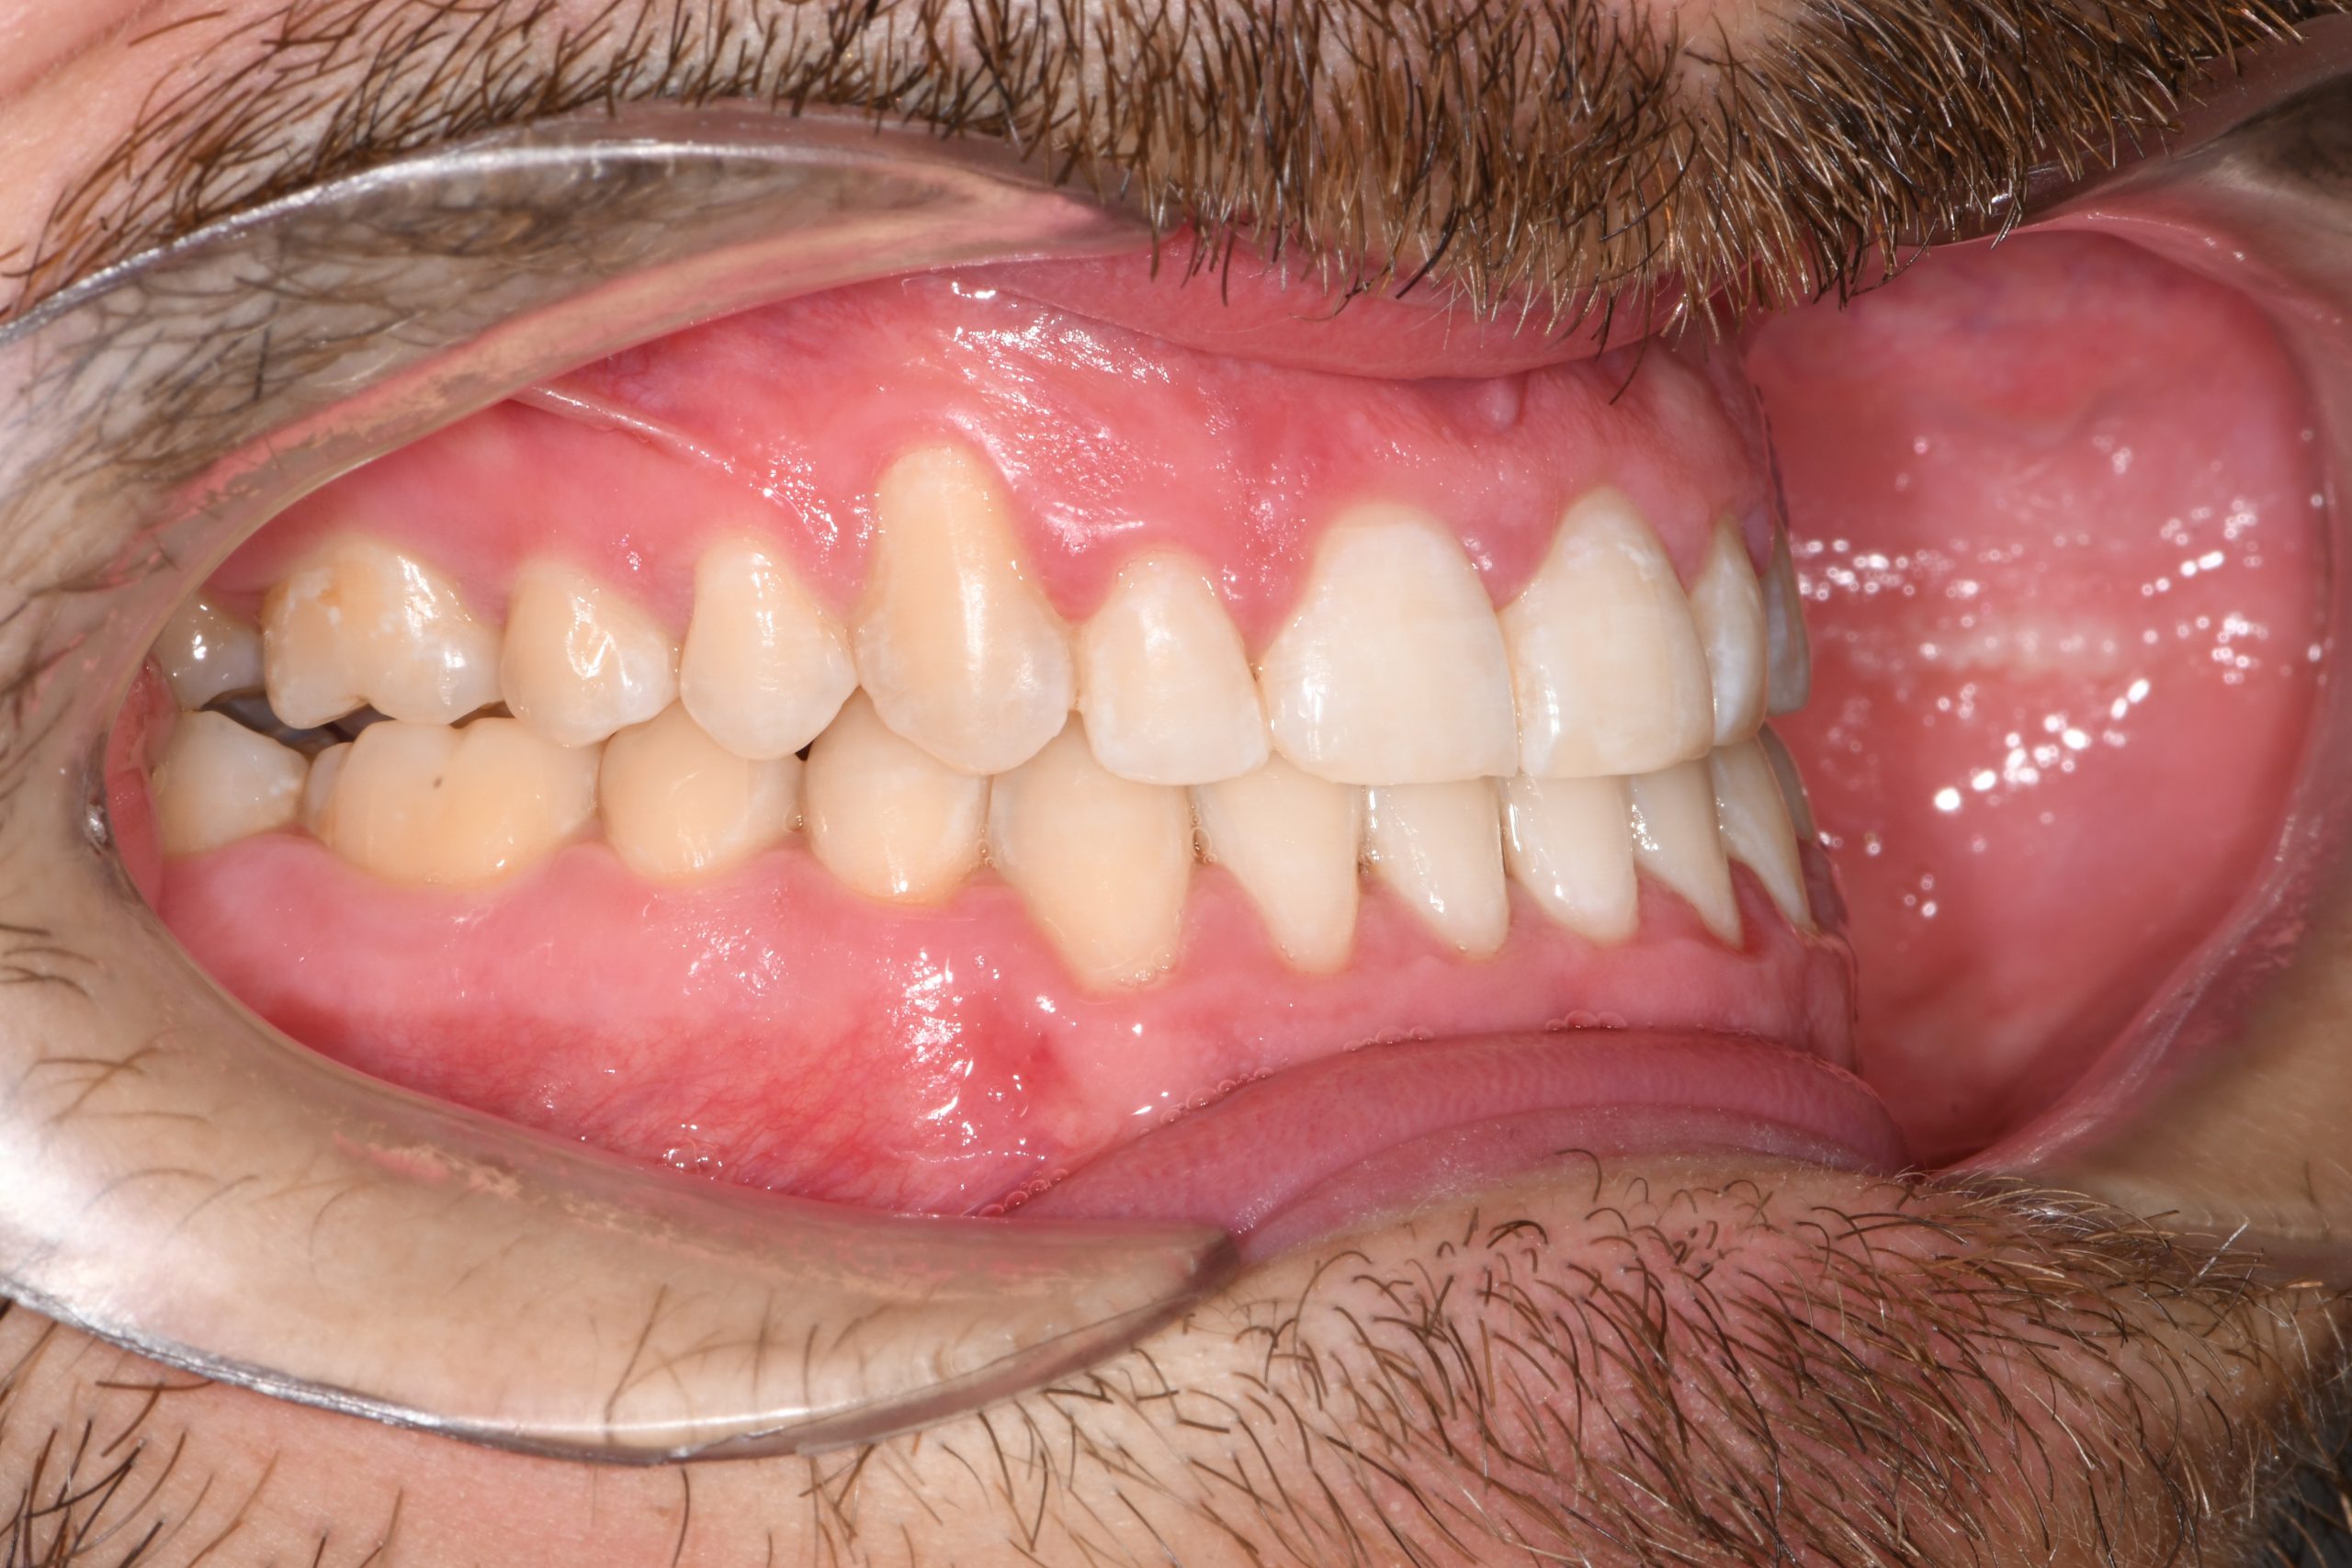

Az elmúlt évekből rengeteg szakmai referenciát tudnánk bemutatni, amelyek különböző fogszabályozási problémákat oldottak meg. Válogatva a több száz esetből, ezen az oldalon olyan képeket, információkat igyekeztünk bemutatni, amelyeknek a segítségével a jövőbeni pácienseinknek azt tudjuk üzenni: A Te fogsorod is lehet gyönyörű!

(Képeket a Pácienseink külön írásos beleegyezésével mutatjuk be!)